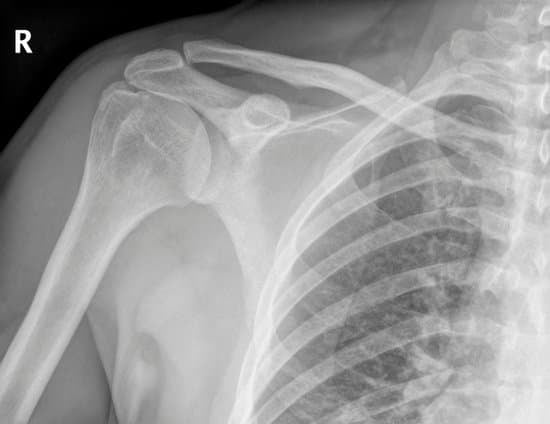

영상 진단: X-레이를 통한 어깨 질환 평가

X-레이는 어깨 질환을 진단할 때 가장 기본적으로 사용되는 영상 검사 방법으로, 골격 구조와 관절 상태를 확인하는 데 효과적입니다.

1) 골절

어깨뼈(견갑골), 쇄골, 상완골 등의 뼈가 부러진 상태 확인.

골절 위치, 형태(선상 골절, 분쇄 골절 등), 변위를 평가.

2) 탈구

어깨 관절(견관절)이 본래 위치에서 벗어난 상태.

전방 탈구가 가장 흔하며, 후방 탈구는 드물게 발생.

X-레이로 관절의 변형, 위치 이상 확인.

3) 관절염

관절 연골이 닳아 발생하는 퇴행성 질환.

X-레이로 관절 간격 축소, 골극(뼈의 돌출) 형성, 관절강 내 석회화 등을 확인.

X-레이는 골격 관련 어깨 질환(골절, 탈구, 관절염)을 신속히 평가하는 데 효과적인 검사 방법입니다.

하지만 연부 조직 손상이나 관절 내부 세부 구조 확인에는 MRI, CT, 초음파 등의 추가 검사가 필요할 수 있습니다.